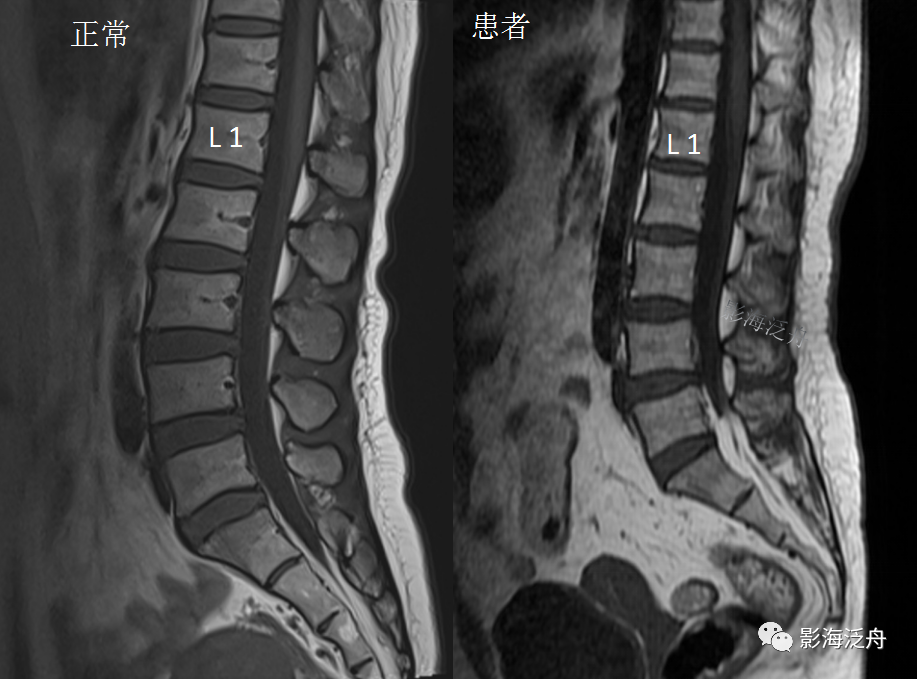

正常的腰骶部MR解剖:在脊髓圆锥(红箭)水平以下,椎管内走行的主要是终丝及马尾神经(黄箭),大量脑脊液填充在硬膜囊内(蓝箭头);硬膜囊以外的椎管内只有少量脂肪组织填充(绿箭头)。

为了方便大家记忆,笔者标注了一个腰椎矢状切面解剖标本,用来跟正常腰椎MR图像对照观察。

最后,把正常和异常图像放一起再次对比观察,加深记忆!

(注:上面两幅图都是T1WI,由于是不同厂家仪器扫描,所以图像质感有差异)